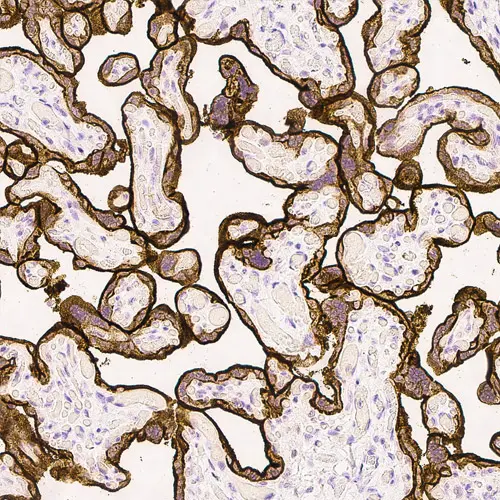

Human placenta: immunohistochemical staining for Epidermal Growth Factor Receptor. High expression of EGFR localized in the trophoblastic layer of the placental villi. Epidermal Growth Factor Receptor: clone EGFR.113

Klon EGFR.25 wurde auf die zytoplasmatische Domäne des EGFR-Moleküls und Klon EGFR.113 auf die extrazelluläre Domäne abgestimmt.